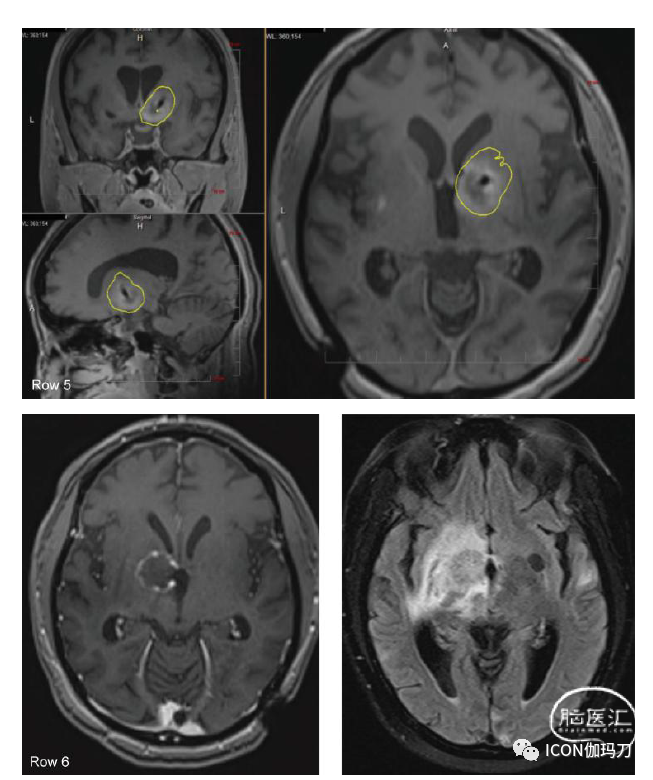

对于不太容易外科手术接近的病变,一种更近期的外科技术称为激光热凝固术(laser thermocoagulation)或激光间质热治疗(laser interstitial thermotherapy,LITT)已经发展起来,以满足组织诊断和治疗放射性坏死的需要。自十年前推出以来,它被越来越多地使用,包括在标准开颅手术可治疗病变的患者中。这部分是因为该技术的微创性,尽管在大多数中心,这些患者仍然需要全身麻醉。在此过程中,在头皮上做一个小的刺入切口和在颅骨上做一个5毫米的钻孔,以帮助病变活检首先提供诊断。然后,沿着相同的轨迹,病变可以使用二极管激光进入病变中心进行消融。激光发出的光在周围的组织中转化为热。然后使用连续术中MR梯度回波成像监测热传递的进程。然后使用专有软件计算实时消融图,利用每个成像体素处于升高温度的时间,使外科医生能够监测并确定消融何时完成(图36.5)。术后患者通常需要在夜间观察,由于切口小且没有开颅手术,很少需要疼痛管理。大多数患者可以在术后第一天回家。

图36.5(第1排)肺癌患者在接受18 Gy的 SRS治疗后1年维持TKI,且右侧基底神经节病变再次生长。(第2行)在LITT手术开始时,激光纤维被立体定向地放置在肿瘤中间(白色轮廓)。上面3排是消融图,黄色圆圈显示从激光光纤周围开始热扩散的位置。(第三排)手术后期,黄色圆圈表示热通过病灶扩散。(第4行和第5行)LITT治疗消融完成时在治疗软件窗口和标准解剖平面估计区域的黄色轮廓包围肿瘤。(第6行)LITT后2周T1加权钆剂增强和 MRI的FLAIR序列显示强化病灶大小稳定,脑水肿早期减少。(第7行)LITT治疗后6周,病灶尺寸减小,周围脑水肿减少。